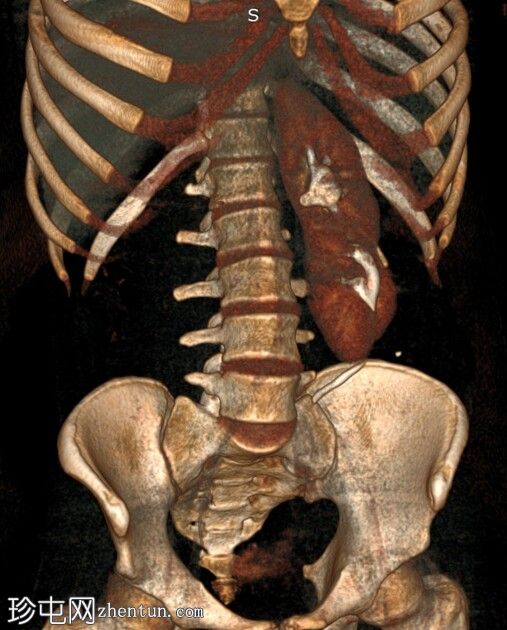

3.jpg

轴位CT图像显示双肾位于腹部左侧,肾实质融合,符合交叉融合性肾异位。延迟期图像证实双侧输尿管均正常开口于膀胱,右侧输尿管跨越中线开口于右侧膀胱输尿管连接处。